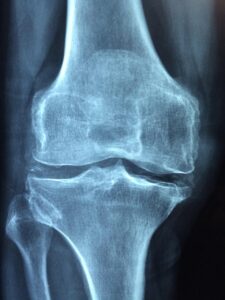

RTG Kolena

POLIKLINIKA PROSEK pokračuje v cyklu pravidelných měsíčních akcí zaměřených na zdraví a prevenci. Listopadovým tématem je osteoporóza, která představuje jednu z nejčastějších metabolických chorob a